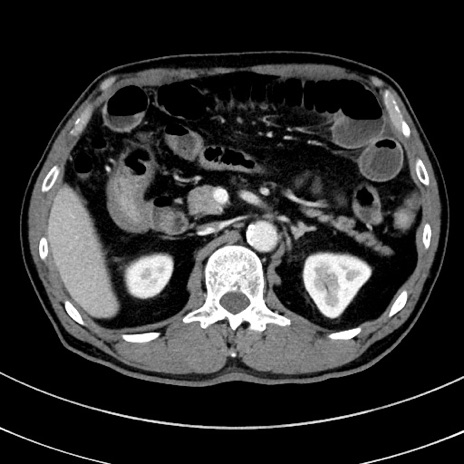

冠状断像

【症例】 60歳代男性

【主訴】 黒色吐物

【現病歴】 4日前から嘔気自覚、2日前の朝食後にも嘔気あり、自分で手で嘔吐反射起こし嘔吐したところ血が混ざっていたため受診。

【既往歴】 5年前汎発性腹膜炎を伴う急性虫垂炎で手術、高血圧、前立腺肥大症、高脂血症

【身体所見】 腹部正中に手術癩痕あり 腹部平坦・軟圧痛なし膨満感あり

【データ】WBC 8400、CRP 4.54